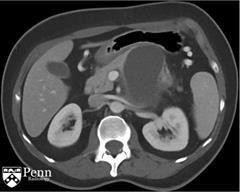

马女士, 55岁,左腰痛。腹部增强CT如下图所示。

于胰体/尾部的巨大的分叶状的囊性肿块,包绕脾动脉。其内可见一致密物在病变的内部下方与其分层。脾静脉内形成血栓,导致明显的胃肝和胃脾静脉曲张。见一假性动脉瘤起源于脾静脉的分支。

诊断:粘液性囊性肿瘤伴低度不典型增生,仅局限于胰腺,邻近慢性胰腺炎和假性囊肿形成伴囊内血栓。